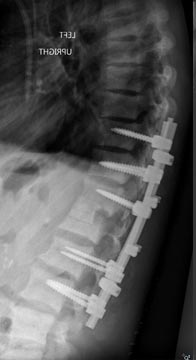

73 year old woman with osteoporosis who fell and fractured her pelvis. She was unable to walk and developed lumbopelvic dissociation (seperation of the spine from the pelvis and lower half of the body) from an unstable sacral fracture and displacement.

Lumbopelvic fixation with prophylactic cement augmentation and patient was immediately able to walk again.